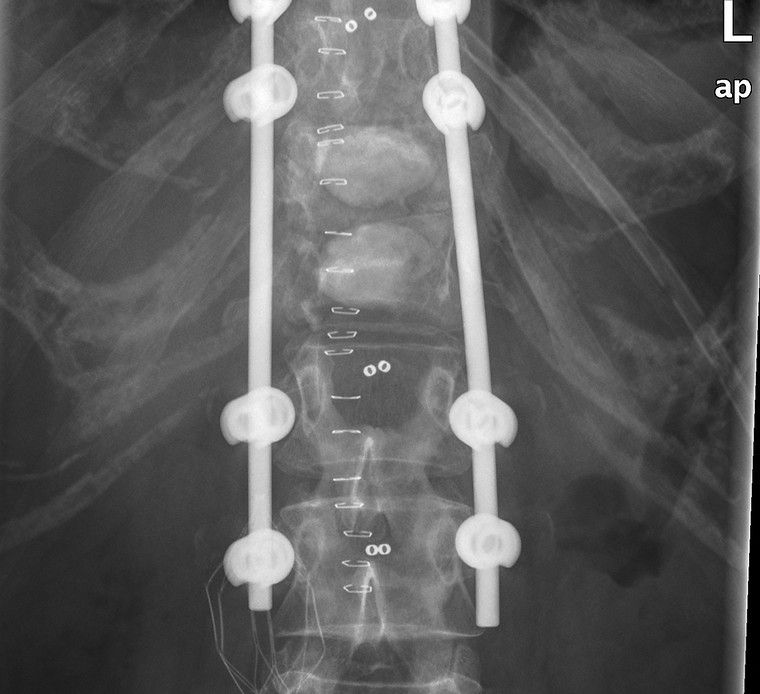

Als Facharzt für Orthopädie lag mein Schwerpunkt als Oberarzt im Wirbelsäulenteam des AKH Wien von 2019 bis 2024 auf der operativen Versorgung von Erkrankungen der Wirbelsäule. In den vergangenen Jahren habe ich viele hundert Wirbelsäulenoperationen durchgeführt – von mikrochirurgischen Eingriffen bis hin zu minimalinvasiven rekonstruktiven Verfahren. Dank meiner langjährigen Erfahrung verfüge ich über besondere Expertise in Bandscheibenoperationen, Dekompressionen sowie in der chirurgischen Behandlung schwerer Wirbelsäulenpathologien. Diese Eingriffe erfordern höchste Präzision, Sorgfalt und ein tiefes Verständnis der individuellen Krankheitsbilder. Besonders wichtig ist mir dabei, Sie umfassend zu beraten und gemeinsam mit Ihnen die für Sie beste Therapieentscheidung zu treffen. Ich nehme mir ausreichend Zeit für Ihre Fragen und sorge dafür, dass Sie sich medizinisch wie menschlich gut aufgehoben fühlen.

Rekonstruktive Wirbelsäulenchirurgie

Wirbelsäulenpathologien werden durch minimalinvasive rekonstruktive Eingriffe versorgt.